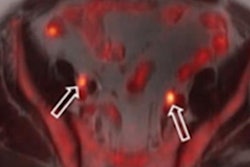

Among the adverse thermal reports, a definitive cause for 348 cases (39%) could not be determined. However, 257 submissions (28%) cited burns from contact with coils (54%), electrocardiography (ECG) electrodes or leads (15%), patient clothing (5%), stereotaxic head frames (4%), blankets (4%), orthopedic implants (3%), and tattoos/permanent makeup (2%) as the cause(s) for patient issues.

"A surprising finding of our analysis was that the MR coils were often cited as the likely cause of burn injuries, such as when coils were routed directly over the patient, patients were in contact with coil cables, or only when sheets or blankets were used to separate coil cables from the patient," Delfino told virtual attendees.

Of particular note were 97 injuries (10%) that occurred when large patients came in contact with the sides of the bore when they were positioned off-center for shoulder and breast exams, for example.